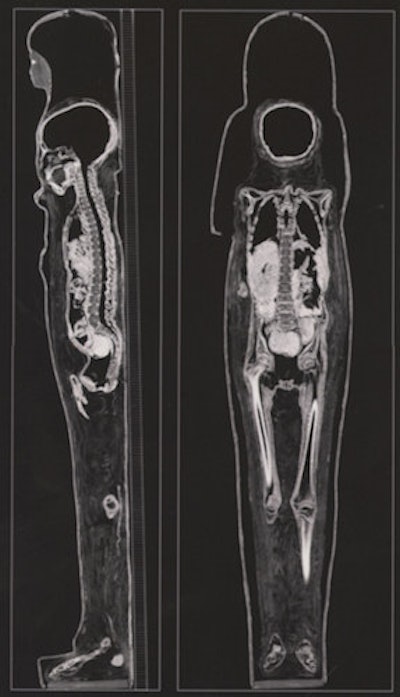

There is an exciting exhibition at the British Museum titled Ancient lives new discoveries: Eight mummies, eight stories. These eight mummies are examined using modern scanners and produce astonishing images. The older x-ray techniques have been replaced by the latest generation of dual-energy CT scanners. In a similar way to the older physical unwrapping, the modern CT scan can produce a virtual unwrapping, removing the various layers of the body down to the skeleton.

This reveals detailed biological information. The information was analyzed using methods developed by forensic archaeologists and physical anthropologists. Information about diet, the state of health, and the embalming techniques that were used are obtained. In the exhibition, the eight mummies are displayed with supporting material including the CT scan. The CT images are projected and can be virtually unwrapped and manipulated by the visitor using a touch-sensitive controller.

The CT can be directly compared with the adjacent mummy. I found the experience most remarkable. It emphasized to me the essential humanity of the mummies that were being examined, with the images looking like the CT scans that are reported every day. We are therefore looking at human beings who are the same as we are, and we are not looking at museum objects. These are people who lived and breathed and had feelings in the same manner that we do.